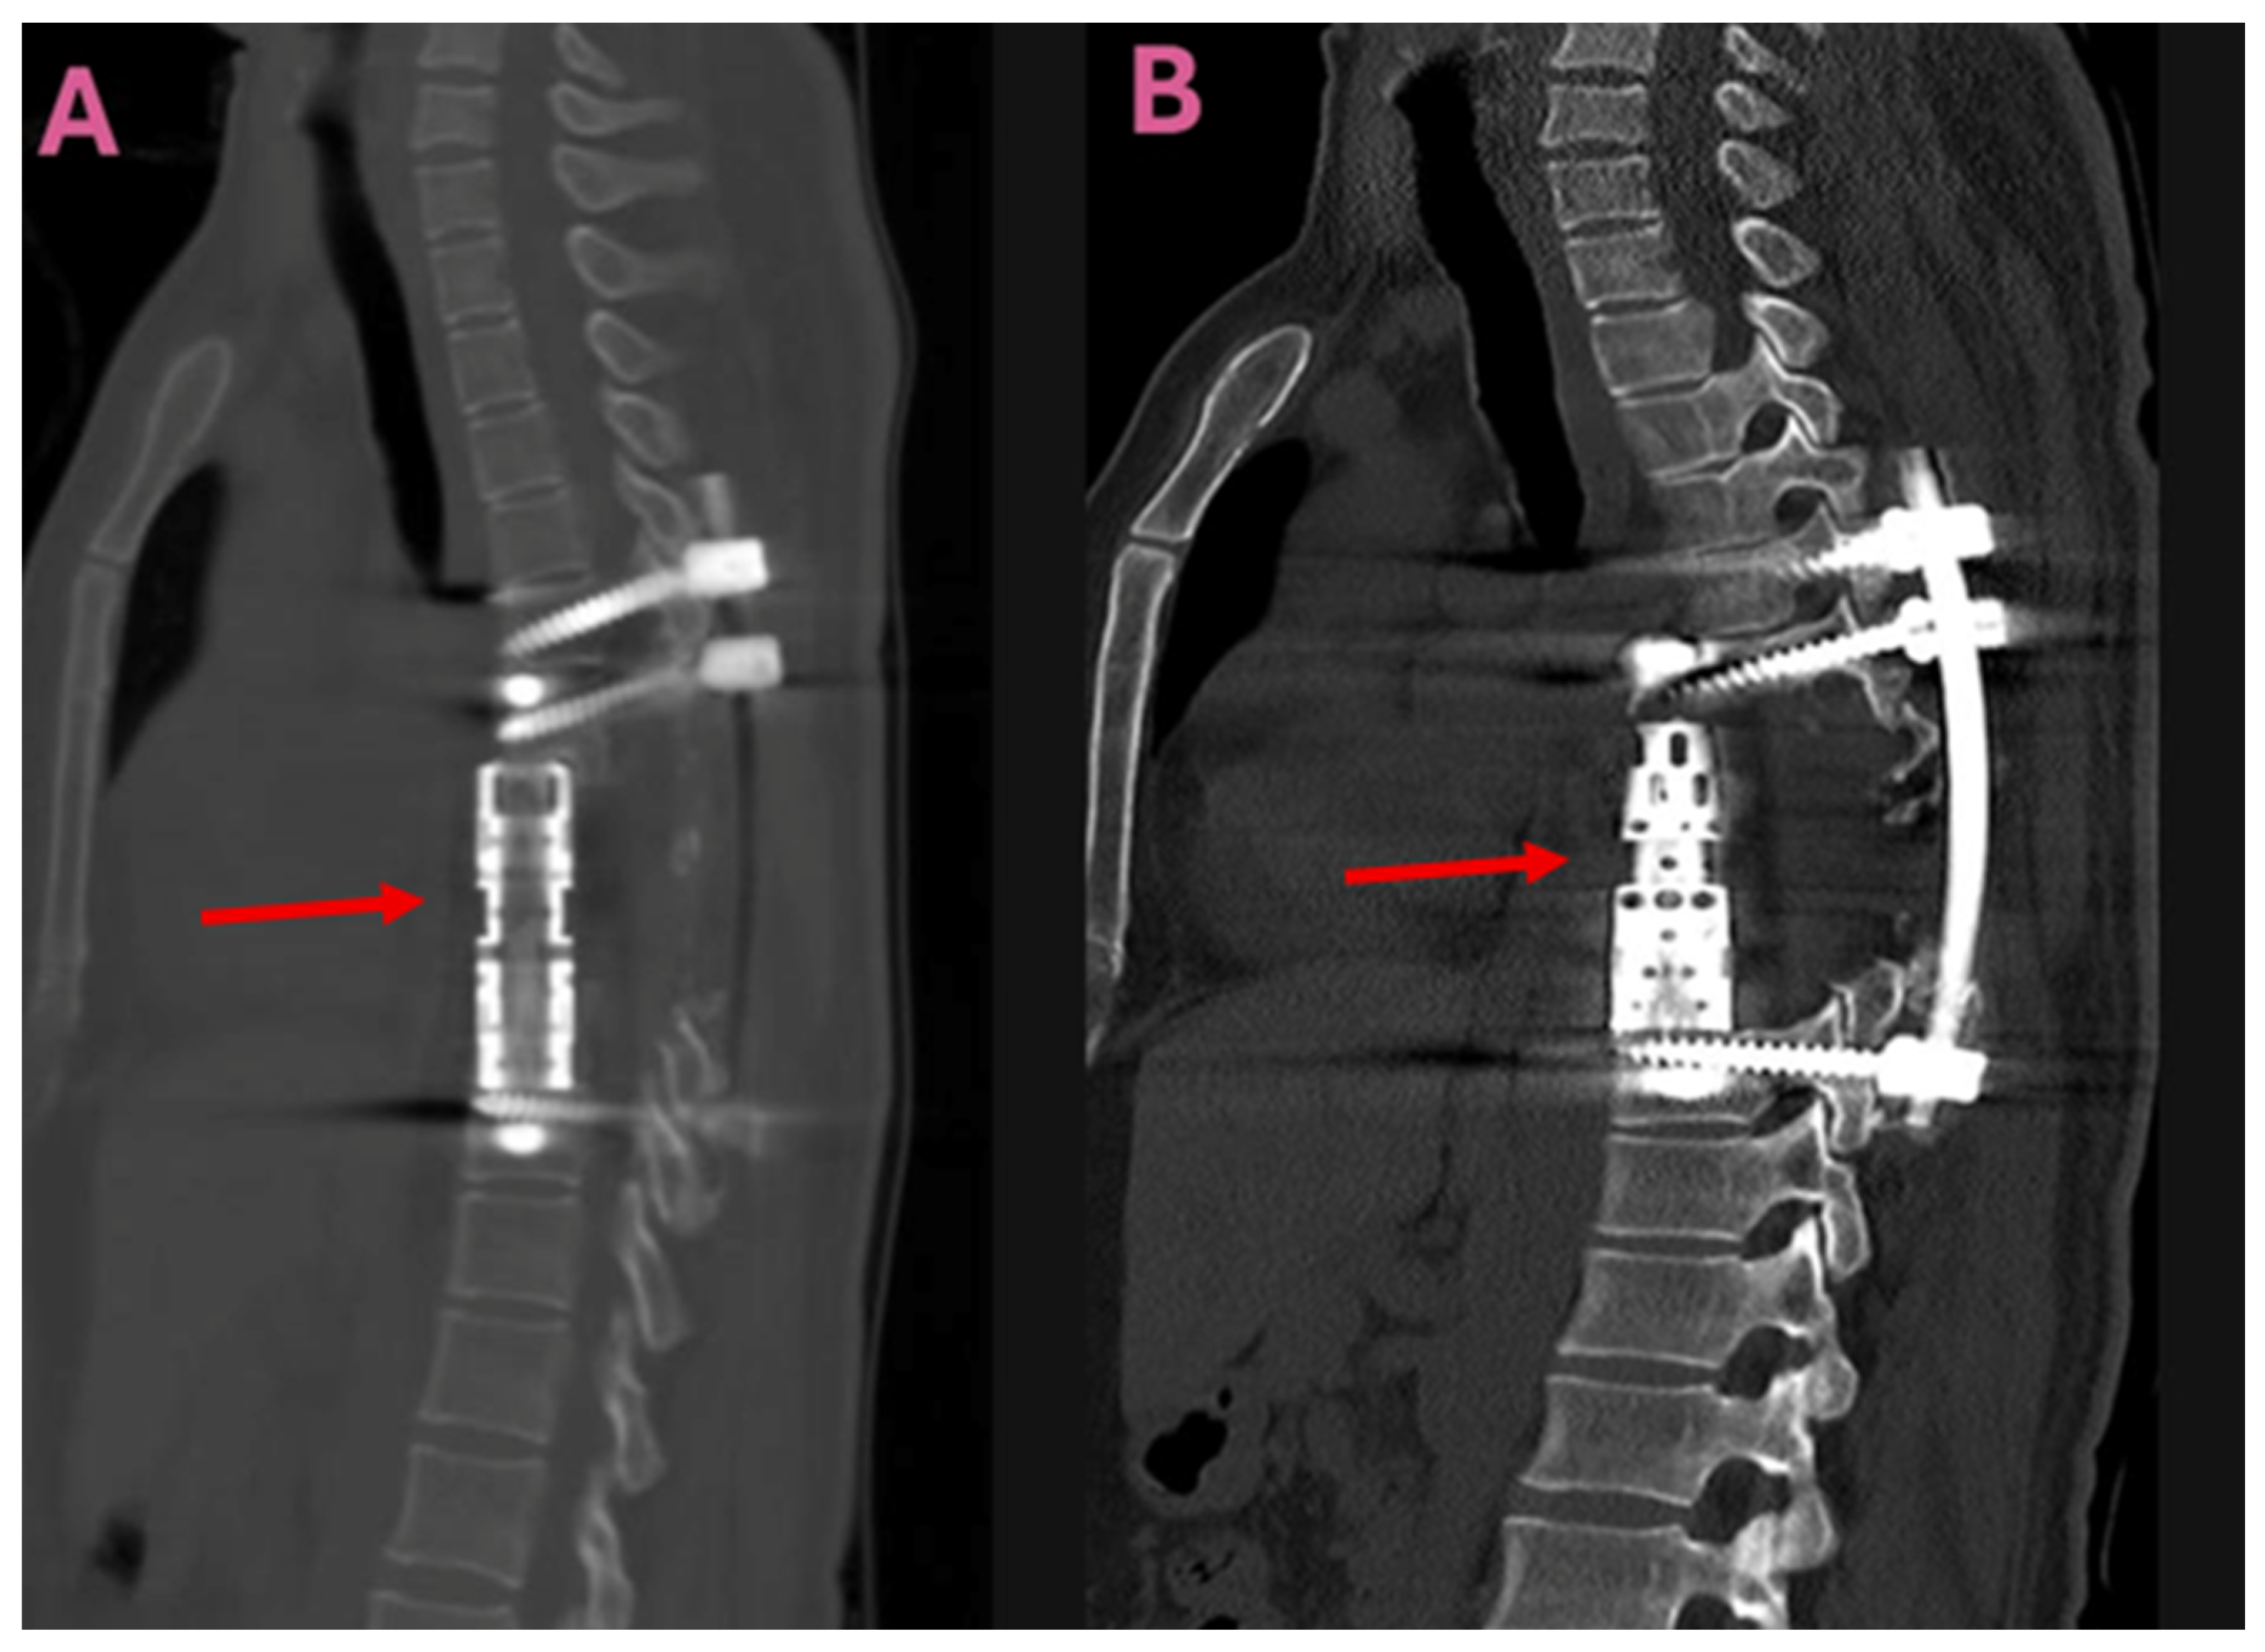

Depending on the surgical method used, the patients were assessed in two groups. Group 1 (TES group, n = 9) consisted of patients who underwent total en-bloc spondylectomy, anterior column reconstruction with a titanium cage, and posterior instrumentation covering the adjacent levels (Figure 1).

Imaging studies revealed that the lesions involved multiple anatomical structures within the vertebral segment. All the patients in the TES group exhibited vertebral body involvement, while the CLDS patients did not present any corpus involvement (p < 0.001). Posterior element involvement was universal in the CLDS group and was also common in TES patients. Paravertebral extension was noted in both groups. Major spinal canal invasion (>50%) was observed in both groups (Table 2). Representative MRI and CT images are provided in Figure 4 and Figure 5.

Figure 1. Postoperative sagittal CT images taken following total en-bloc spondylectomy (TES) for a thoracic spinal hydatid cyst. (A,B): Sagittal CT scans demonstrating vertebral body reconstruction and posterior instrumentation. Arrows indicate the titanium interbody cage used for vertebral body reconstruction. Abbreviations: CT, computed tomography; TES, total en-bloc spondylectomy.